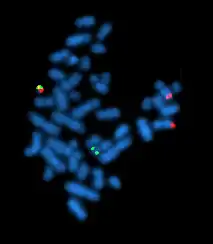

Cytogenetics is essentially a branch of genetics, but is also a part of cell biology/cytology (a subdivision of human anatomy), that is concerned with how the chromosomes relate to cell behaviour, particularly to their behaviour during mitosis and meiosis.[1] Techniques used include karyotyping, analysis of G-banded chromosomes, other cytogenetic banding techniques, as well as molecular cytogenetics such as fluorescence in situ hybridization (FISH) and comparative genomic hybridization (CGH).

Fluorescence in situ hybridization

Fluorescence in situ hybridization (FISH) refers to using fluorescently labeled probe to hybridize to cytogenetic cell preparations.

Analysis of FISH specimens is done by fluorescence microscopy by a clinical laboratory specialist in cytogenetics. For oncology, generally, a large number of interphase cells are scored in order to rule out low-level residual disease, generally between 200 and 1,000 cells are counted and scored. For congenital problems usually 20 metaphase cells are scored.